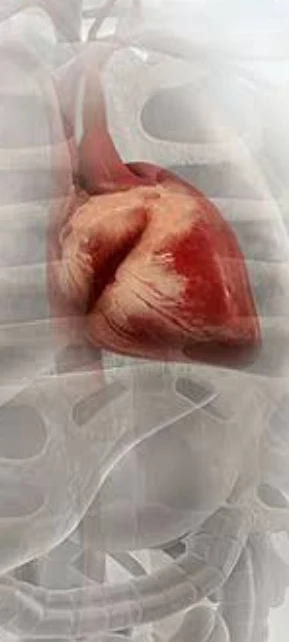

Silent Heart Attack

For many silent heart attack patients, the symptoms are confusing, worsening, and potentially life-threatening.

Just hearing the word heart attack creates some kind of fear in everyone. A heart attack does not come without any symptoms. Most people don't notice them or don't even know they are symptoms of a heart attack. But now some common symptoms predict a heart attack on their own. What are the symptoms of a silent heart attack? Unpredictable. Unlike a typical heart attack, silent heart attacks are more likely to be painless. For many silent heart attack patients, the symptoms are confusing, worsening, and potentially life-threatening.

What is a silent heart attack?

In any type of heart attack, blood flow to the heart is blocked. Fatty plaques in the arteries and blood vessels cause blockages, restricting the flow of oxygen to the heart. Same with Silent Heart Attack. But the symptoms are sometimes mild. Sometimes it doesn't even exist.